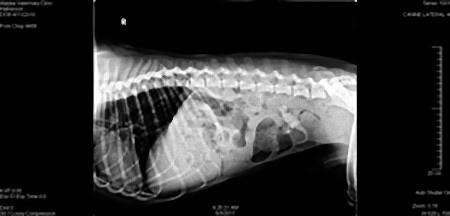

優勝写真:

犬が飲み込んだナインボールズ